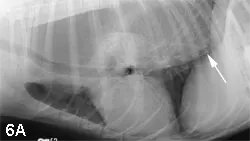

Esophageal abnormalities (foreign body, abnormal distension with ventral deviation of the trachea, mass lesions (Figure 6)

Right lateral (A) and ventrodorsal (B) images from a dog with generalized megaesophagus secondary to myasthenia gravis. Note the ventral deviation of the trachea and heart in the cranial and middle mediastinum. In addition, the dorsal, ventral, and lateral borders of the caudal thoracic radiograph converge to the esophageal hiatus in the central, dorsal third of the diaphragm (arrows).